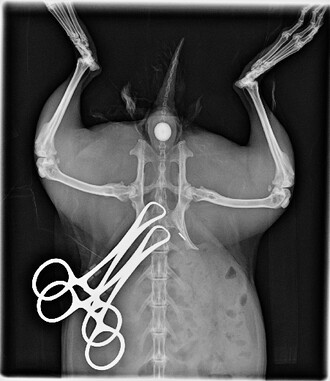

O těch nemám moc přehled, ale na veterinárních školách jistě bude v projektu pokusu například naučení se operačních technik na potkanovi. A etická komise na této škole např. zhodnotí, zda byla vybrána současná adekvátní narkóza. A je jasné, že pokud se má lékař humánní nebo veterinární naučit operovat, musí začít na potkanech či králících. A také je zřejmé, že na jiných školách takový projekt pokusů s velkou pravděpodobností neuvidíte.

Pitva, zvláště pak obratlovců, není jen individuální zjištění, že orgány, o kterých se žák učil, tam skutečně jsou. Je to bezprostřední kontakt s matérií, který je doprovázen silným emočním nábojem. Ten zážitek je důležitý. To se nedá vyčíst z knížky, jak se střihne do tkáně. Když to žáci vidí na vlastní oči, líp si to pamatují, protože je to provázené právě tím emočním nábojem, tou vybuzeností. A k úplné exaltaci docházelo, když studenti zoologie měli možnost operovat zvíře v narkóze. Mám s tím osobní zkušenosti. I po mnoha letech absolventi na toto praktikum vzpomínají jako na jeden z nejdůležitějších vzdělávacích momentů, kterým prošli.